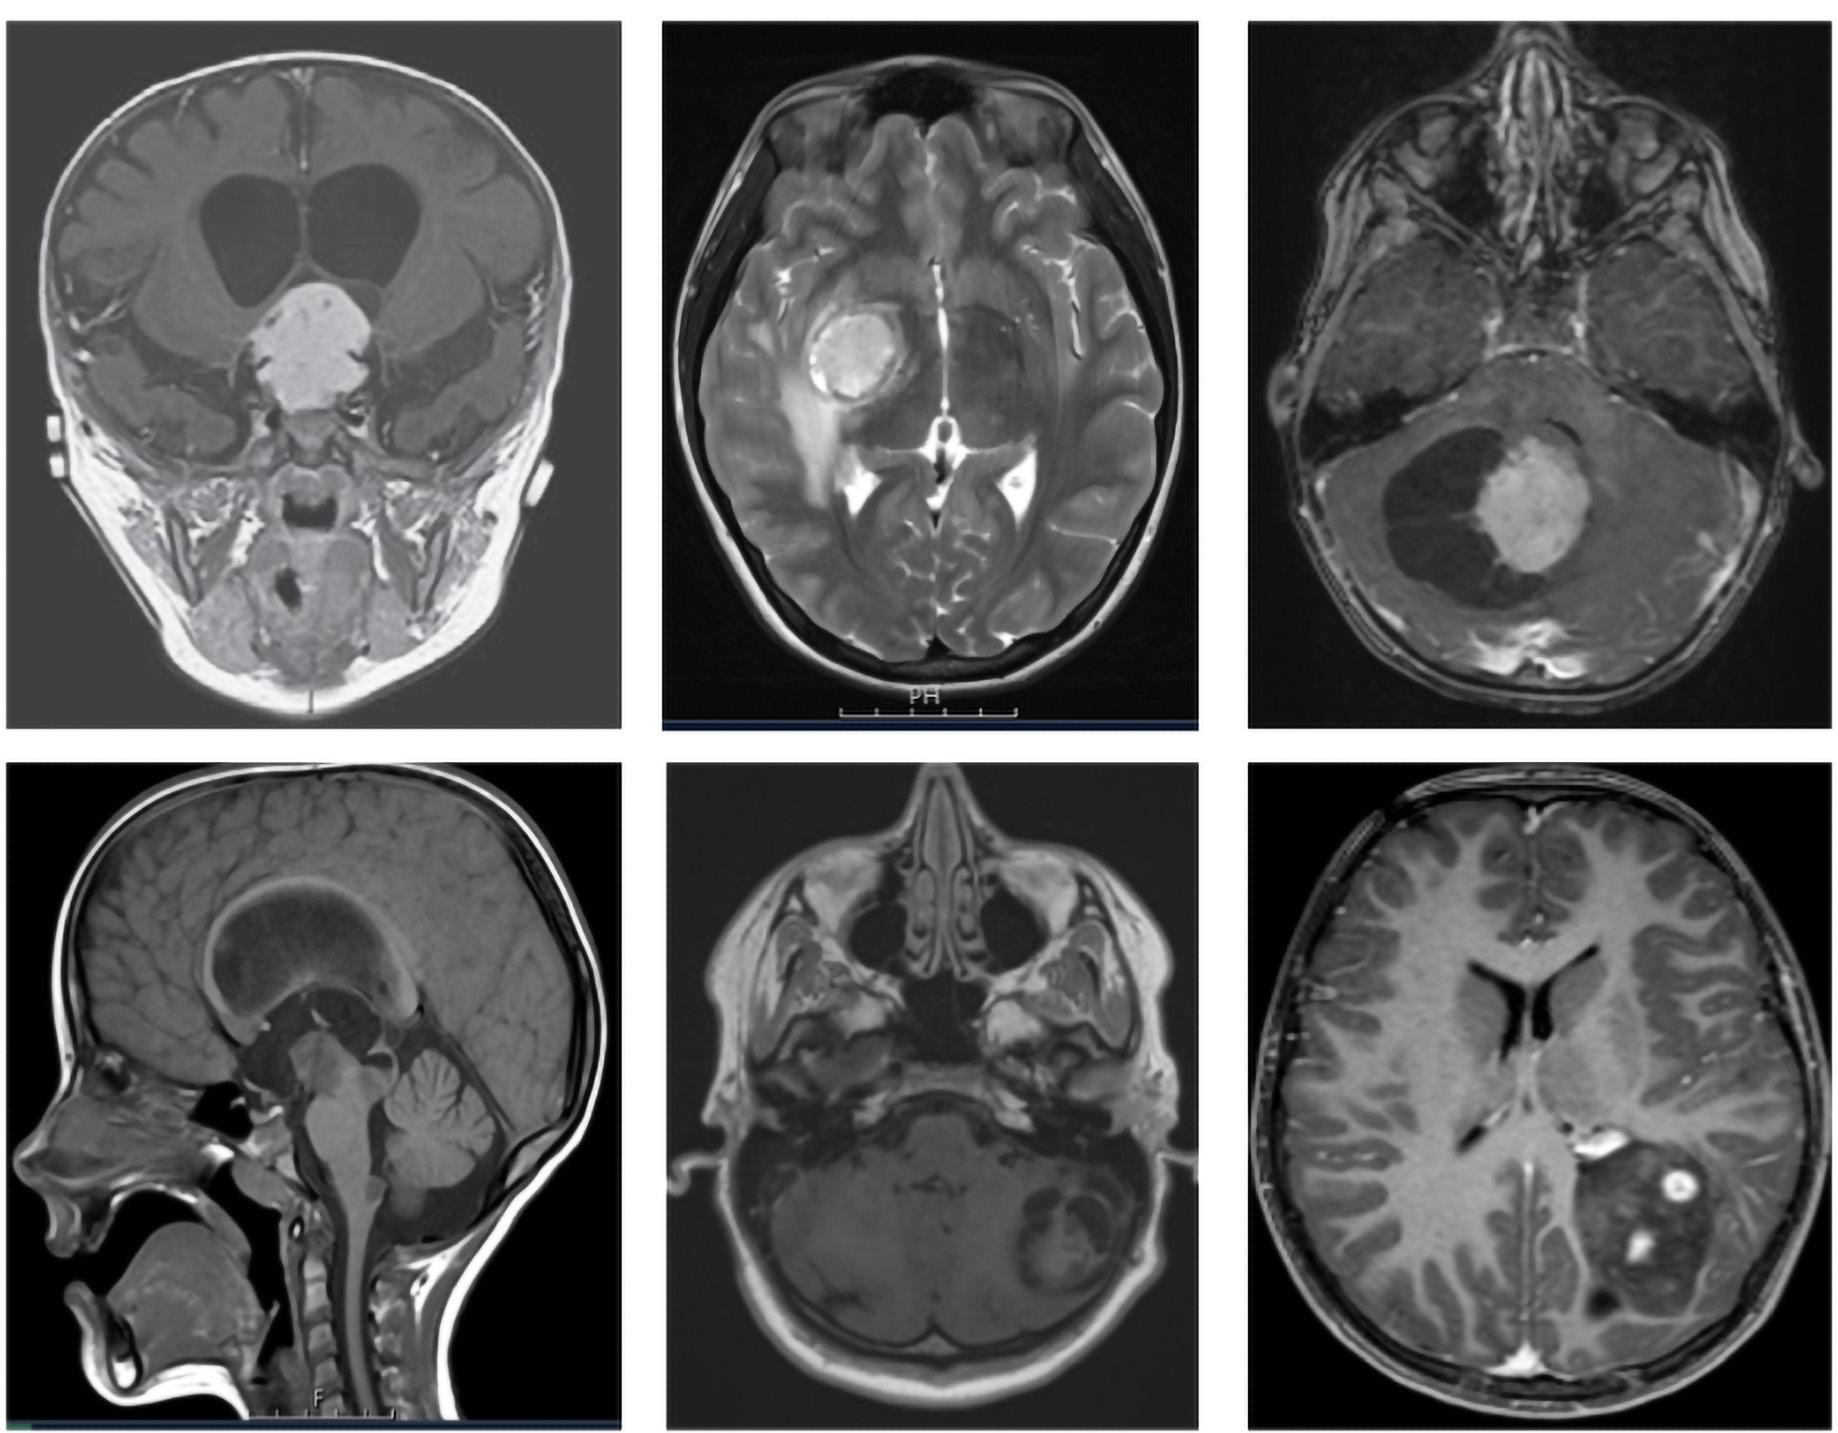

FIGUR 1: MR-bildene viser tydelig heterogenitet i hjernesvulster hos barn. A – Pilocytisk astrocytom i synsnerve (WHO grad ­1); B – Diffust astrocytom (WHO grad – 2); C – Høygradig gliom (WHO grad – 4); D – Diffust midtlinjegliom (WHO grad – 4); E ­ Dysembryoplastisk nevroepitelial tumor (WHO grad – 1); F – Gangliogliom (WHO grad – 1); G – Supratentorielt ependymom (WHO grad – 3); H – Pilocytisk astrocytom (WHO Grad – 1); I – Medulloblastom ( WHO grad – 4); J – Medulloblastom (WHO grad – 4); K – Ependymom ( WHO grad – 4); L ­ Glionevronaltumor forenlig med RGNT ( WHO – Grad 1). Alle pasienter har samtykket til bruk av bildene.

Gliomer utgjør den største andelen av hjernesvulster hos barn, med pilocytisk astrocytom og andre lavgradige gliomer som de mest vanlige typene (Figur 3). Embryonale svulster, særlig medulloblastom, er også hyppige. I motsetning til voksne, der meningeomer og glioblastomer dominerer, preges barnepopulasjonen av utviklingsrelaterte og lavgradige svulster. Dette har betydning for

Hjernesvulster er den vanligste formen for solide kreftsvulster hos barn og utgjør omtrent 30% av alle krefttilfeller i barne- og ungdomsalder. Til tross for betydelige fremskritt innen diagnostikk og behandling, er hjernesvulster fortsatt en ledende årsak til kreftrelatert dødelighet hos barn. Behandlingen krever en tverrfaglig tilnærming med høyspesialisert kompetanse, der nevrokirurgi spiller en nøkkelrolle. Fremskritt innen nevrobildediagnostikk, kirurgiske teknikker, molekylærbiologisk diagnostikk, onkologisk behandling og støttebehandling har bidratt til forbedret prognose for flere svulsttyper innenfor sentralnervesystemet. Samarbeid i tverrfaglige team bestående av nevrokirurger, barneonkologer, radiologer, patologer, endokrinologer og rehabiliteringseksperter er avgjørende for best mulig behandling og oppfølging. Denne artikkelen gir en samlet fremstilling av epidemiologi, diagnostikk og behandling av hjernesvulster hos barn og ungdom, med hovedvekt på de vanligste entitetene: gliomer, ependymomer, medulloblastomer, atypisk teratoid/rhabdoid tumor (ATRT) og diffuse midtlinjegliomer (Figur 1).

I Norge diagnostiseres årlig 5,8 tilfeller per 100 000 barn med en hjernesvulst. Hos barn oppstår de fleste svulstene i bakre skallegrop (lillehjerne, fjerde ventrikkel og hjernestamme), mens supratentorielle svulster er vanligere hos voksne (Figur 2).